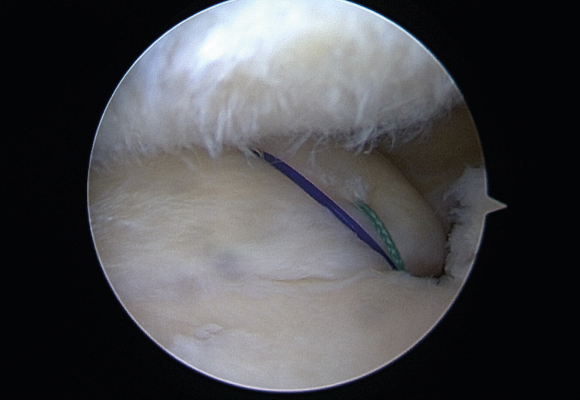

혈관이 있는 부위에 파열이 발생한 경우 연골판을 봉합해 주는 수술 시행

ㆍ환자 동의를 받은 자료이며, 이미지 사진은 실물과 다를 수 있습니다. (22.06.09)